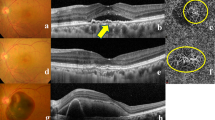

To investigate predictors for macular atrophy (MA) involving the fovea after photodynamic therapy (PDT) followed by pro re nata (PRN) treatment for polypoidal choroidal vasculopathy (PCV).

This prospective observational study analysed treatment-naïve eyes with symptomatic PCV without MA at baseline which were followed up for 5 years. All eyes were initially treated with PDT, followed by a PRN regimen of anti-vascular endothelial growth factor (VEGF) therapy and/or PDT. We assigned eyes with and eyes without development of MA involving the fovea 5 years after the initial treatment into MA and non-MA groups, respectively. Baseline parameters and the number of treatments were compared between the two groups.

Seventy-two eyes of 69 consecutive patients were included, and 29 eyes of 29 patients were analysed. Twelve (41%) and 17 (59%) eyes were assigned into the MA and non-MA groups, respectively. There were significant differences in subfoveal choroidal thickness (226.2 ± 47.8 μm vs. 278.8 ± 68.1 μm, P = 0.03) and number of anti-VEGF injections (13.7 ± 9.6 vs. 5.4 ± 5.6, P = 0.007) between the MA and non-MA groups, but not in the number of PDT sessions (P = 0.71). Best-corrected visual acuity at 5 years in the MA group was lower than in the non-MA group (P = 0.048).

Our long-term observation suggests that a thin subfoveal choroid at baseline and many followed anti-VEGF injections in a PRN regimen increase the risk for development of MA involving the fovea 5 years after PDT.